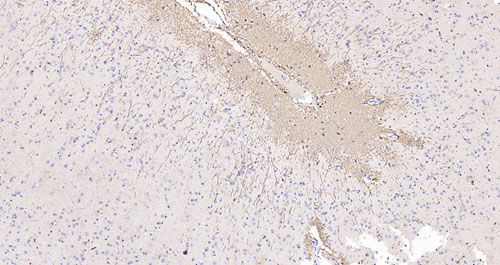

實驗結果展示:

猴腦IHC-GFAP_0.2x

猴腦IHC-GFAP_10.0x